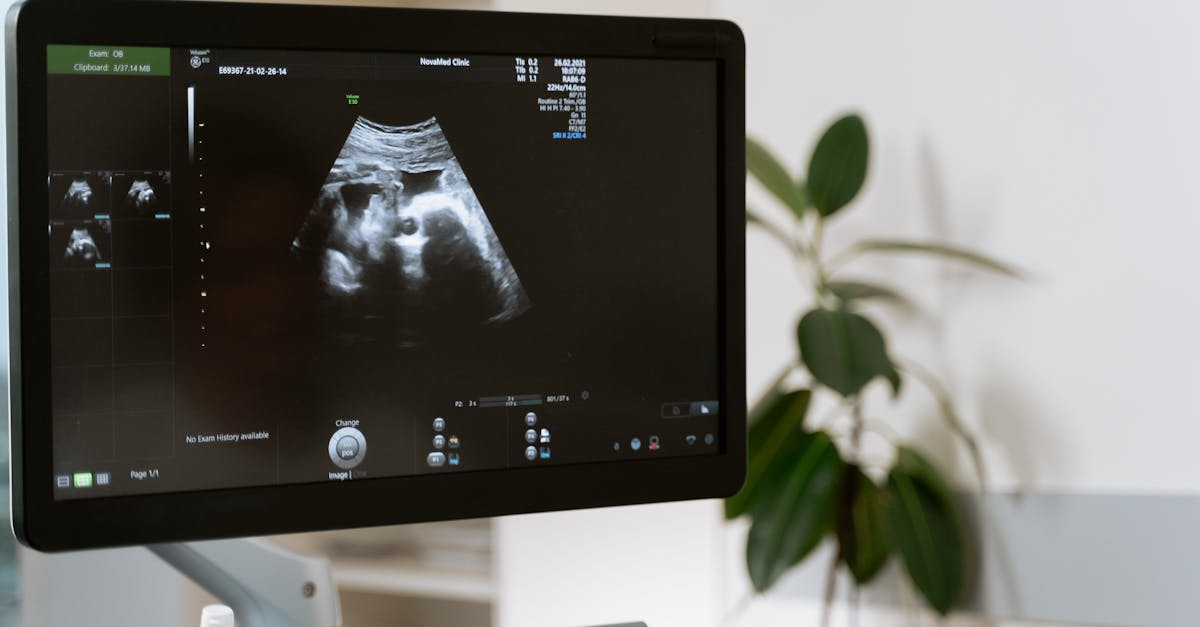

A ultrassonografia com doppler é uma técnica de imagem que permite a visualização do fluxo sanguíneo em tempo real. Utilizada em diversas áreas da medicina, como cardiologia e obstetrícia, ela se destaca por fornecer informações essenciais sobre a circulação e saúde vascular.

imagem ilustrativa

Foto por: MART PRODUCTION via Pexels